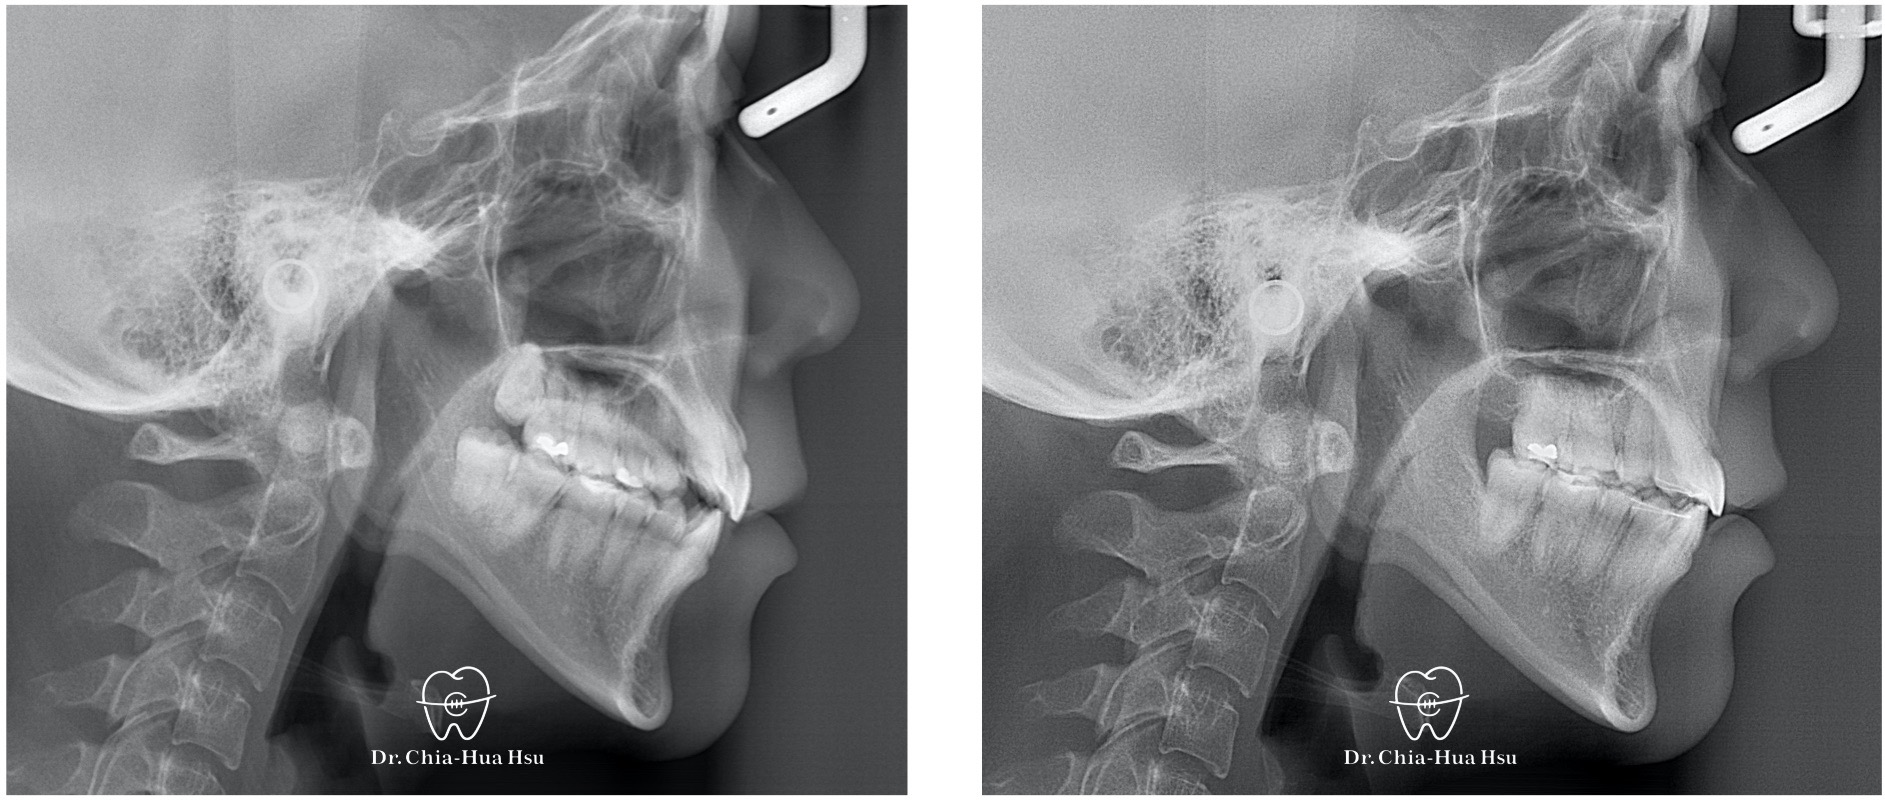

治療前

治療後

- 治療過程:治療過程中,上顎使用上顎頰側與人中骨釘,將上顎齒列往上壓入,改善笑齦。